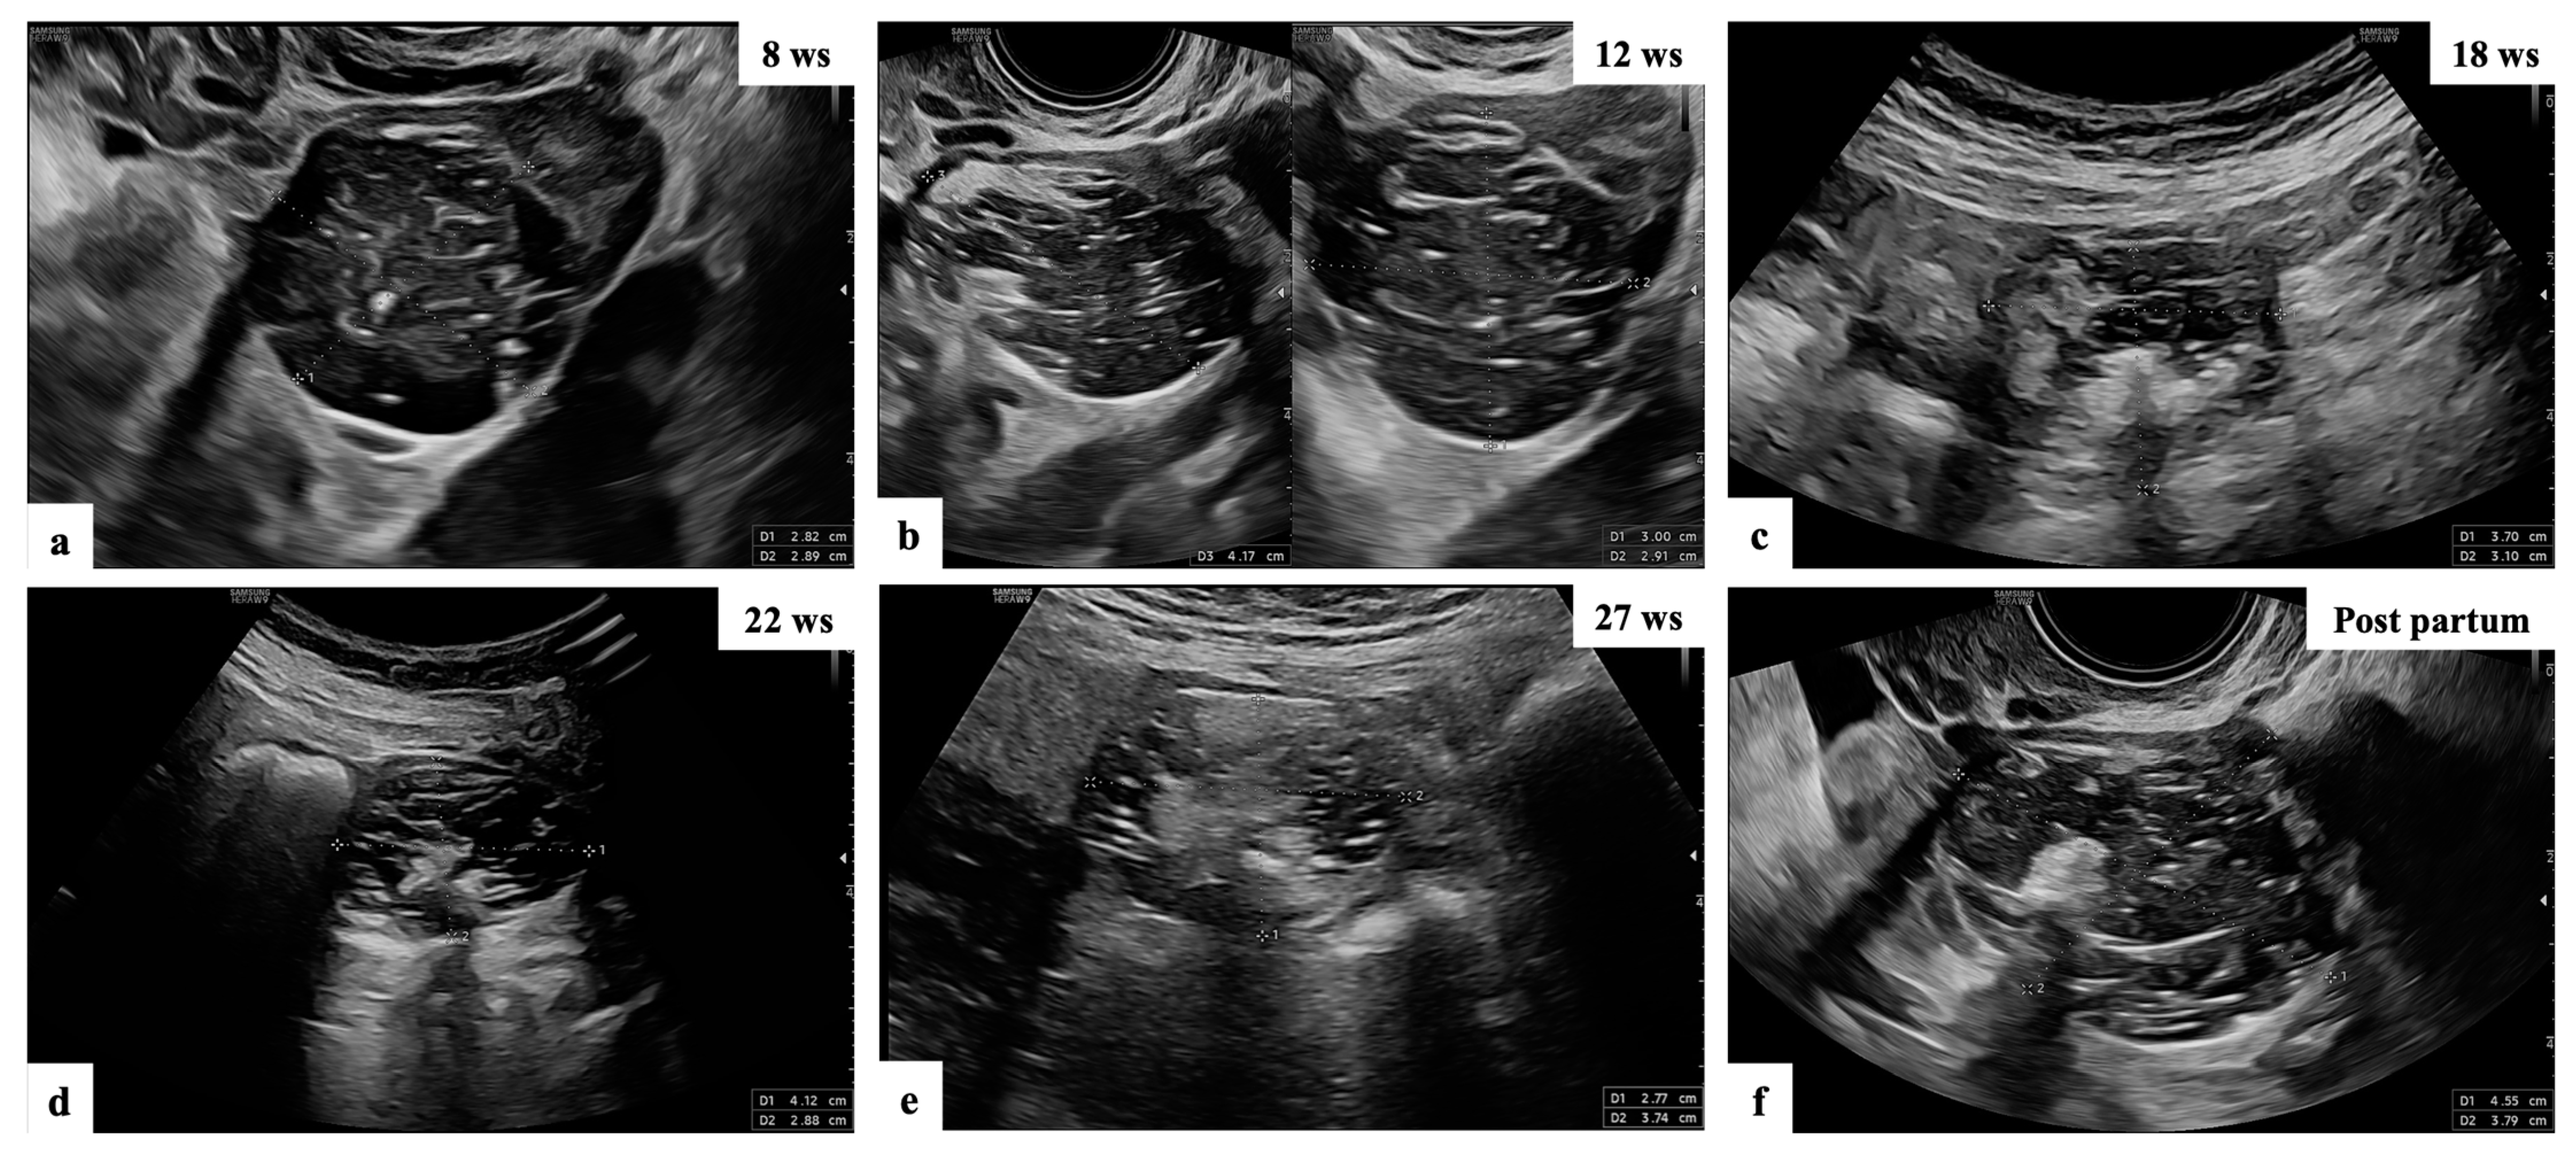

- Mascilini, F.; Moruzzi, C.; Giansiracusa, C.; Guastafierro, F.; Savelli, L.; De Meis, L.; Epstein, E.; Timor-Tritsch, I.E.; Mailath-Pokorny, M.; Ercoli, A.; et al. Imaging in gynecological disease. 10: Clinical and ultrasound characteristics of decidualized endometriomas surgically removed during pregnancy. Ultrasound Obstet. Gynecol. 2014, 44, 354–360. [Google Scholar] [CrossRef]

- Moro, F.; Mascilini, F.; Pasciuto, T.; Leombroni, M.; Li Destri, M.; De Blasis, I.; Garofalo, S.; Scambia, G.; Testa, A.C. Ultrasound features and clinical outcome of patients with malignant ovarian masses diagnosed during pregnancy: Experience of a gynecological oncology ultrasound center. Int. J. Gynecol. Cancer 2019, 29, 1182–1194. [Google Scholar] [CrossRef]

- Pateman, K.; Moro, F.; Mavrelos, D.; Foo, X.; Hoo, W.L.; Jurkovic, D. Natural history of ovarian endometrioma in pregnancy. BMC Women’s Health 2014, 14, 128. [Google Scholar] [CrossRef]